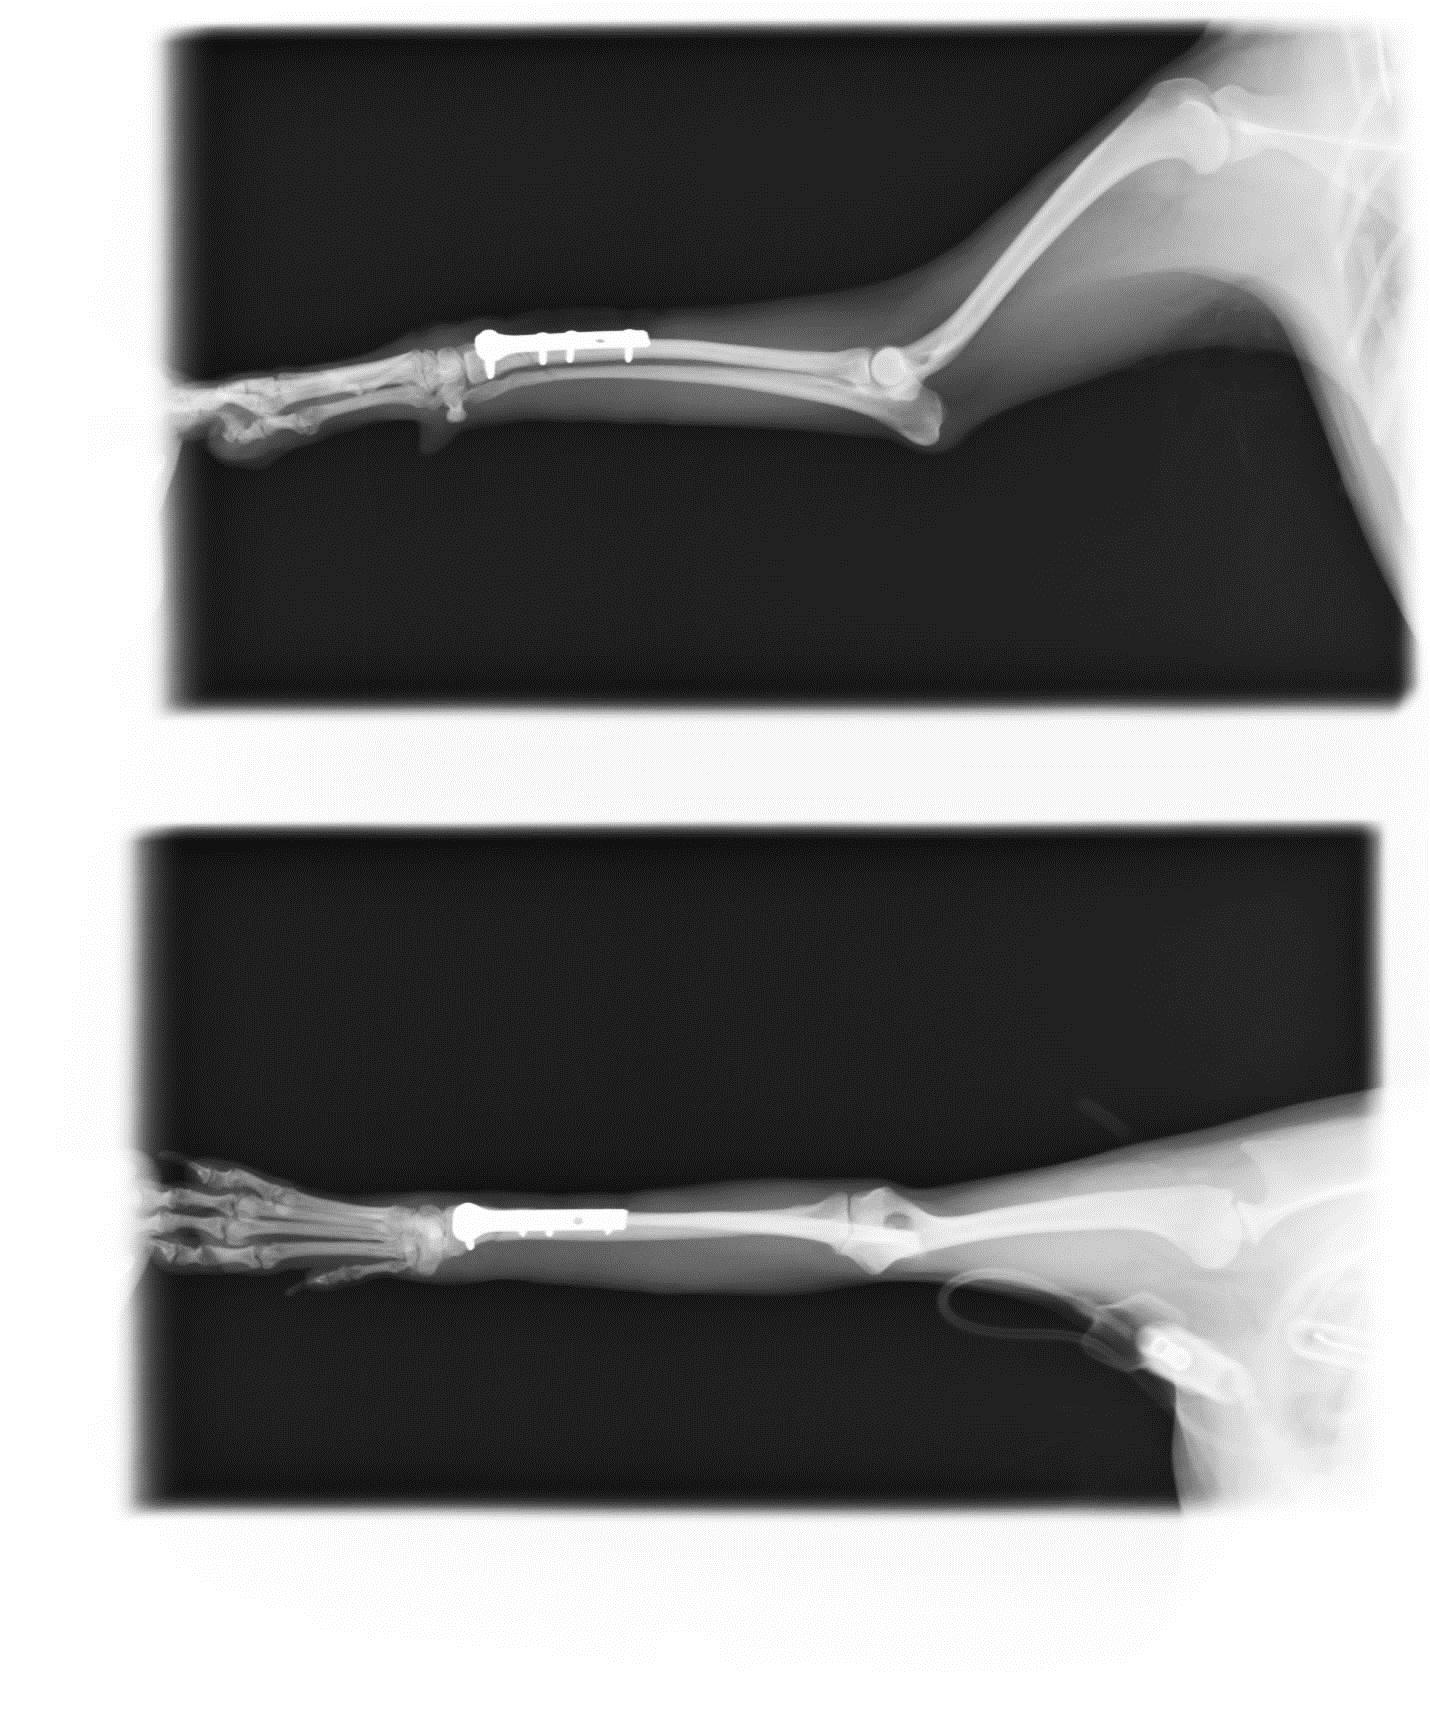

来院時に撮影したレントゲンです。ポッキリと折れてます(=0=)